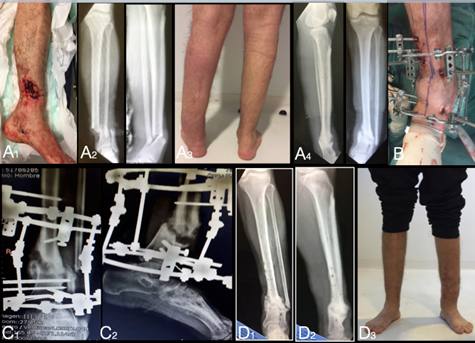

Caso 1

Paciente de 30 años, sexo masculino, trabajador de la construcción. Un año previo a la consulta sufre un accidente de tránsito en moto provocando una fractura expuesta de pierna bilateral. Consulta por dolor, tumefacción local, deformidad evidente del tobillo en varo, sin movilidad del foco fracturario, deambulando con 1 bastón, lo cual le impedía realizar tareas domésticas y laborales. El apoyo del miembro se observaba plantígrado y no presentaba dismetría. La movilidad articular de tobillo, rodilla y cadera era normal, la piel y el examen neurovascular se encontraba sin alteraciones.

Preoperatorio: Al analizar las imágenes nos encontramos con una pseudoartrosis hipertrófica de tibia distal, con una deformidad en el plano oblicuo con un varo en plano frontal y recurvatum en plano sagital sin alteración notoria del plano rotacional. Los estudios de laboratorio eran normales.

Planificamos la cirugía paso a paso en busca de corregir el ángulo mecánico lateral distal tibial (amLDT) alterado. Prearmamos el montaje de fijadores circulares con sus respectivas bisagras de corrección9.

Intraoperatorio: Realizamos osteotomía transversal de peroné a nivel de hueso sano, luego comprobamos la ausencia de movilidad del foco en tibia y colocamos el montaje de Ilizarov siguiendo la deformidad. La duración de la cirugía fue de 60 minutos.

Postoperatorio: Se indicó comenzar movilidad de tobillo y carga de peso parcial desde postoperatorio inmediato. (Figura 1 y 2)